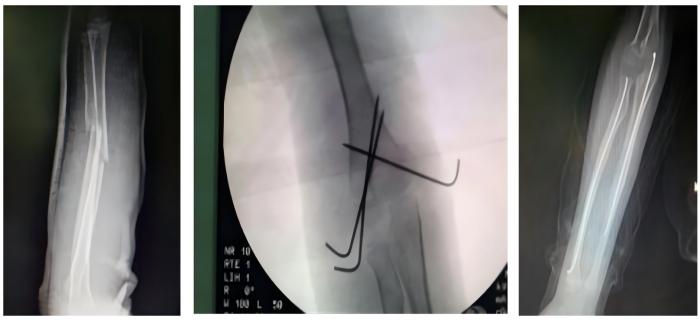

常规开展人体各部位骨折、脱位的修复重建。业务亮点:①我院骨科对于复杂胫骨平台的治疗方法获得国际“平台大师”罗从风教授的高度肯定,并将其编入胫骨平台骨折诊疗教程。②我院骨科通过Stoppa入路,结合传统入路的精髓,治疗复杂骨盆骨折,并在福建省率先使用骨折微创内支架治疗骨盆前环损伤。③对于四肢长管状骨骨折,我院骨科通过几个1-2CM的手术切口,闭合复位骨折,微创插钉,不破坏骨折端软组织及血运。不但减小了手术创伤,还提高了愈合速度。④我院骨科于国内首创使用“微创钛揽捆扎固定”,治疗肩锁关节脱位,完美解决传统手术手术创口大,肩关节活动差,内固定撞击等诸多缺点。

骨折的微创固定手术